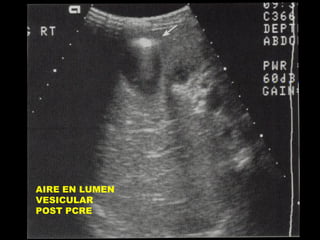

VESICULA CONTRAIDA ALREDEDOR DE

CALCULOS. COLECISTITIS CRONICA

AIRE EN LUMEN

VESICULAR

POST PCRE